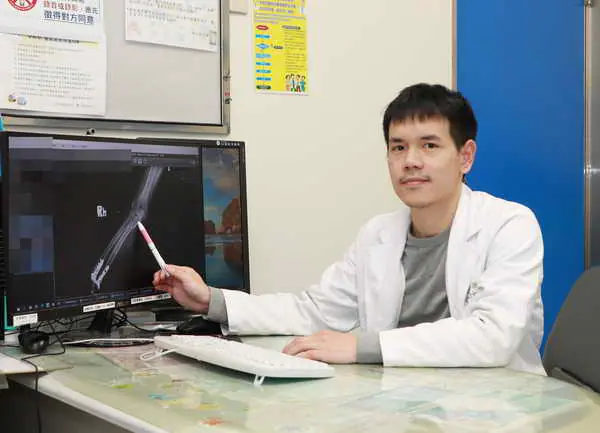

圖一:徐振恆醫師指出,X光片顯示病人的手肘呈現粉碎性骨折。